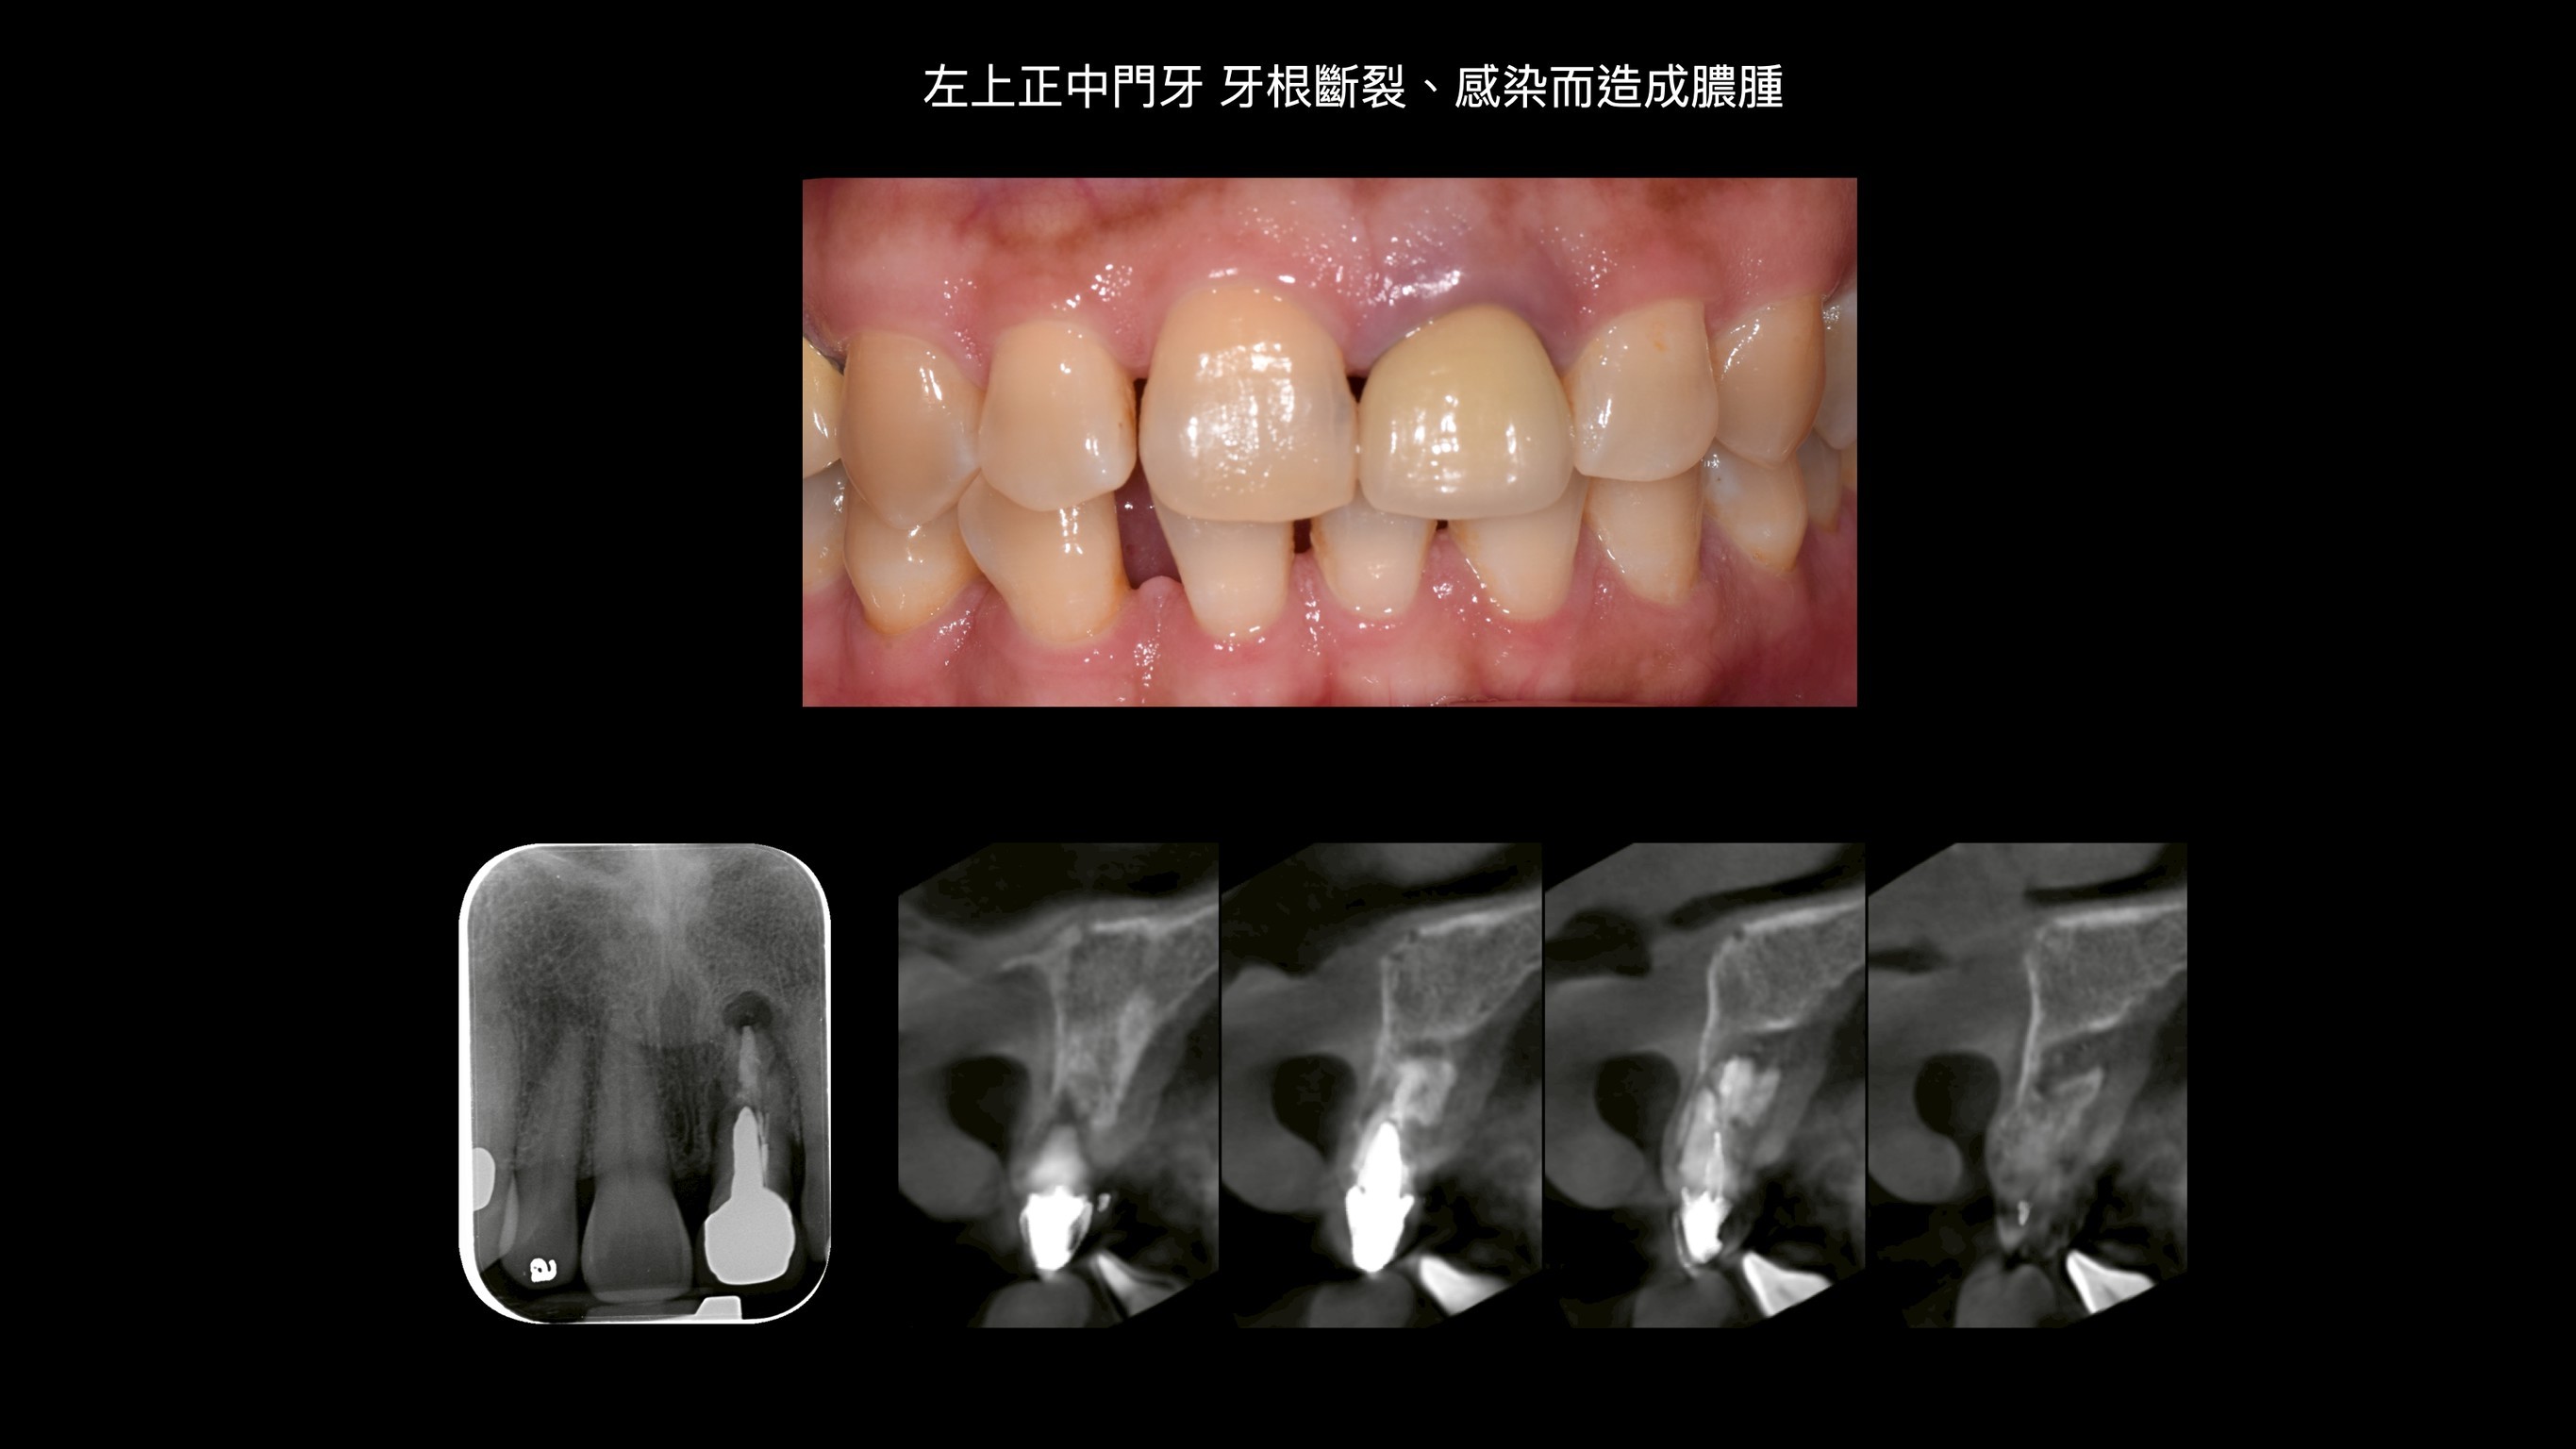

C小姐經其他醫師轉診,因上顎門牙牙根斷裂,感染而造成膿腫,在頰側、顎側、垂直高度皆有嚴重骨缺損。因此在補骨手術中,醫師選擇使用高難度的鈦網合併適度皮瓣減張,可以有效率的達到接近理想的成果。